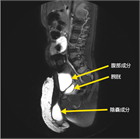

1. エコー検査で陰嚢水瘤であれば、精巣の位置、鼠径部での精巣鞘膜(鞘状突起)の開存、Abdominoscrotal hydroceleの腹腔内成分がないか確認する。